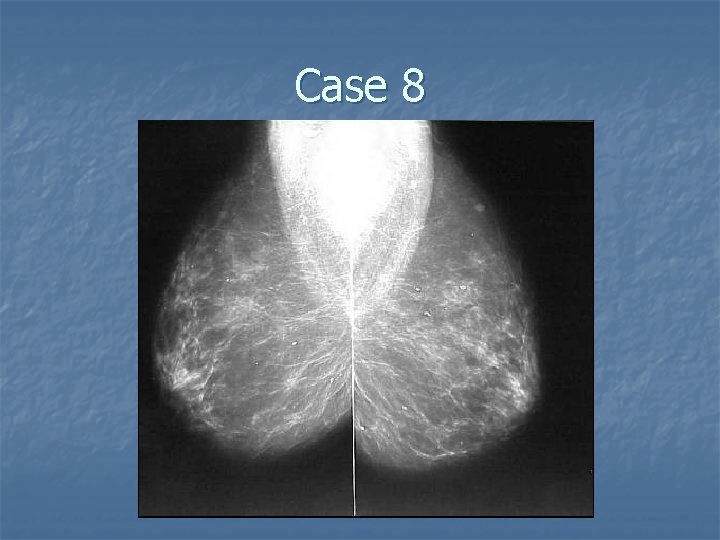

Case 8

Filariasis n Case findings: n n n Mammograms showed unusual serpiginous, tubularwormlike calcifications without an accompanying mass Serpiginous calcifications represent calcified degenerating parasite tissue (filarial granulomas of the breast) Parasite: Wuchereria bancrofti, Brugia malayi